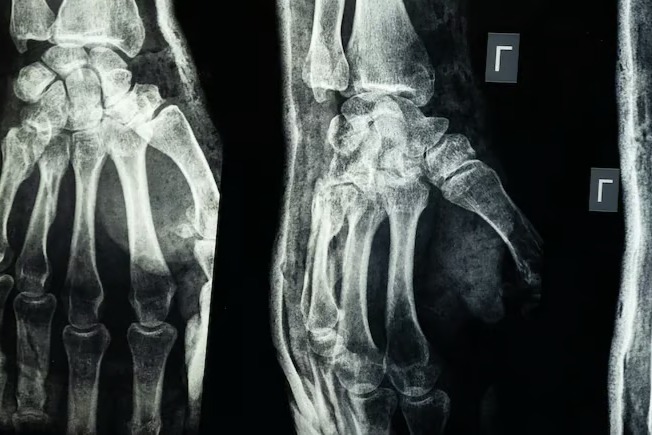

Röntgen filmi - NDTV